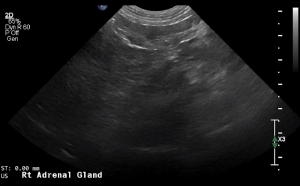

SIMON Ultrasound Database

This ultrasound database is a free resource for students and doctors!

Our collection includes videos of dogs, cats, horses, cows, humans, and many other species!